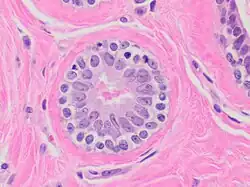

Acini séreux

- Cellule de forme pyramidale

- Lumière étroite

- noyau central arrondi

- Réticulum endoplasmique rugueux (RER) ou granuleux (REG) très développé, cytoplasme souvent basophile

- Présence de grain de sécrétion au pôle apical. Rejette son produit de sécrétion selon un mode mérocrine.

Exemple : acinus pancréatique